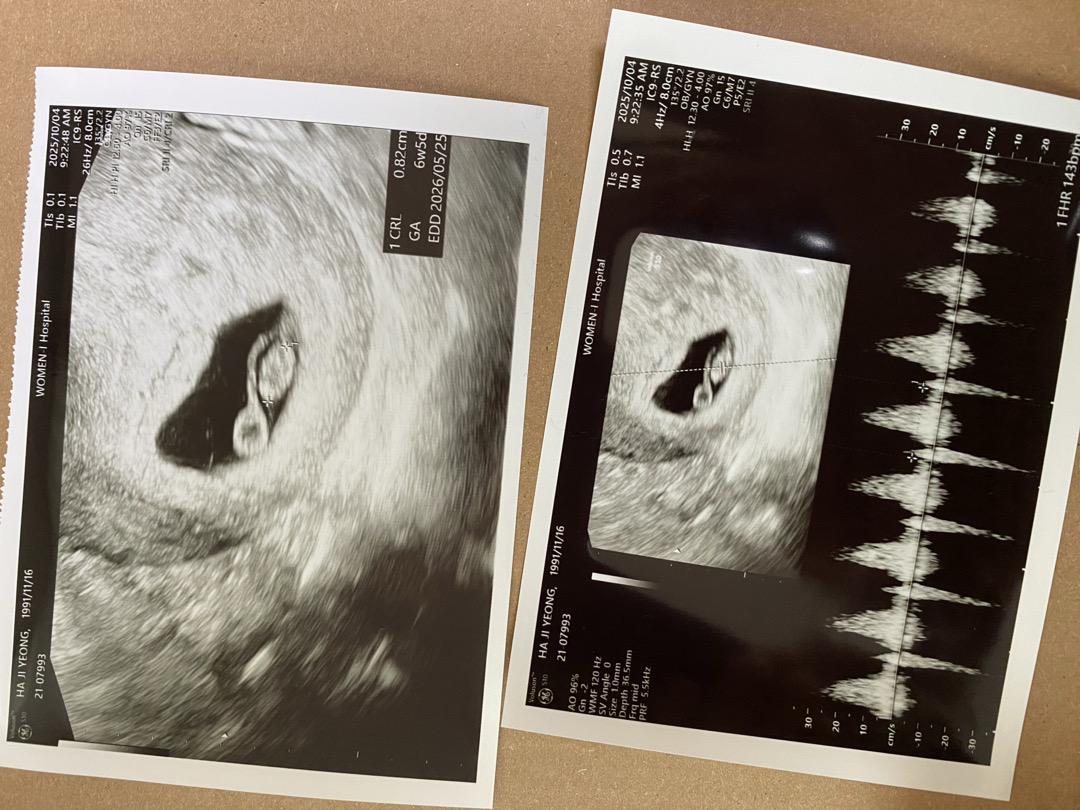

6주 5일 심장소리

쿵떡쿵떡 잘 듣고 왔어요 :) 콕콕 찌름느낌이 있길래 여쭤봤더니 원래 있다고 하셔서 한시름 놨어요 :) 히